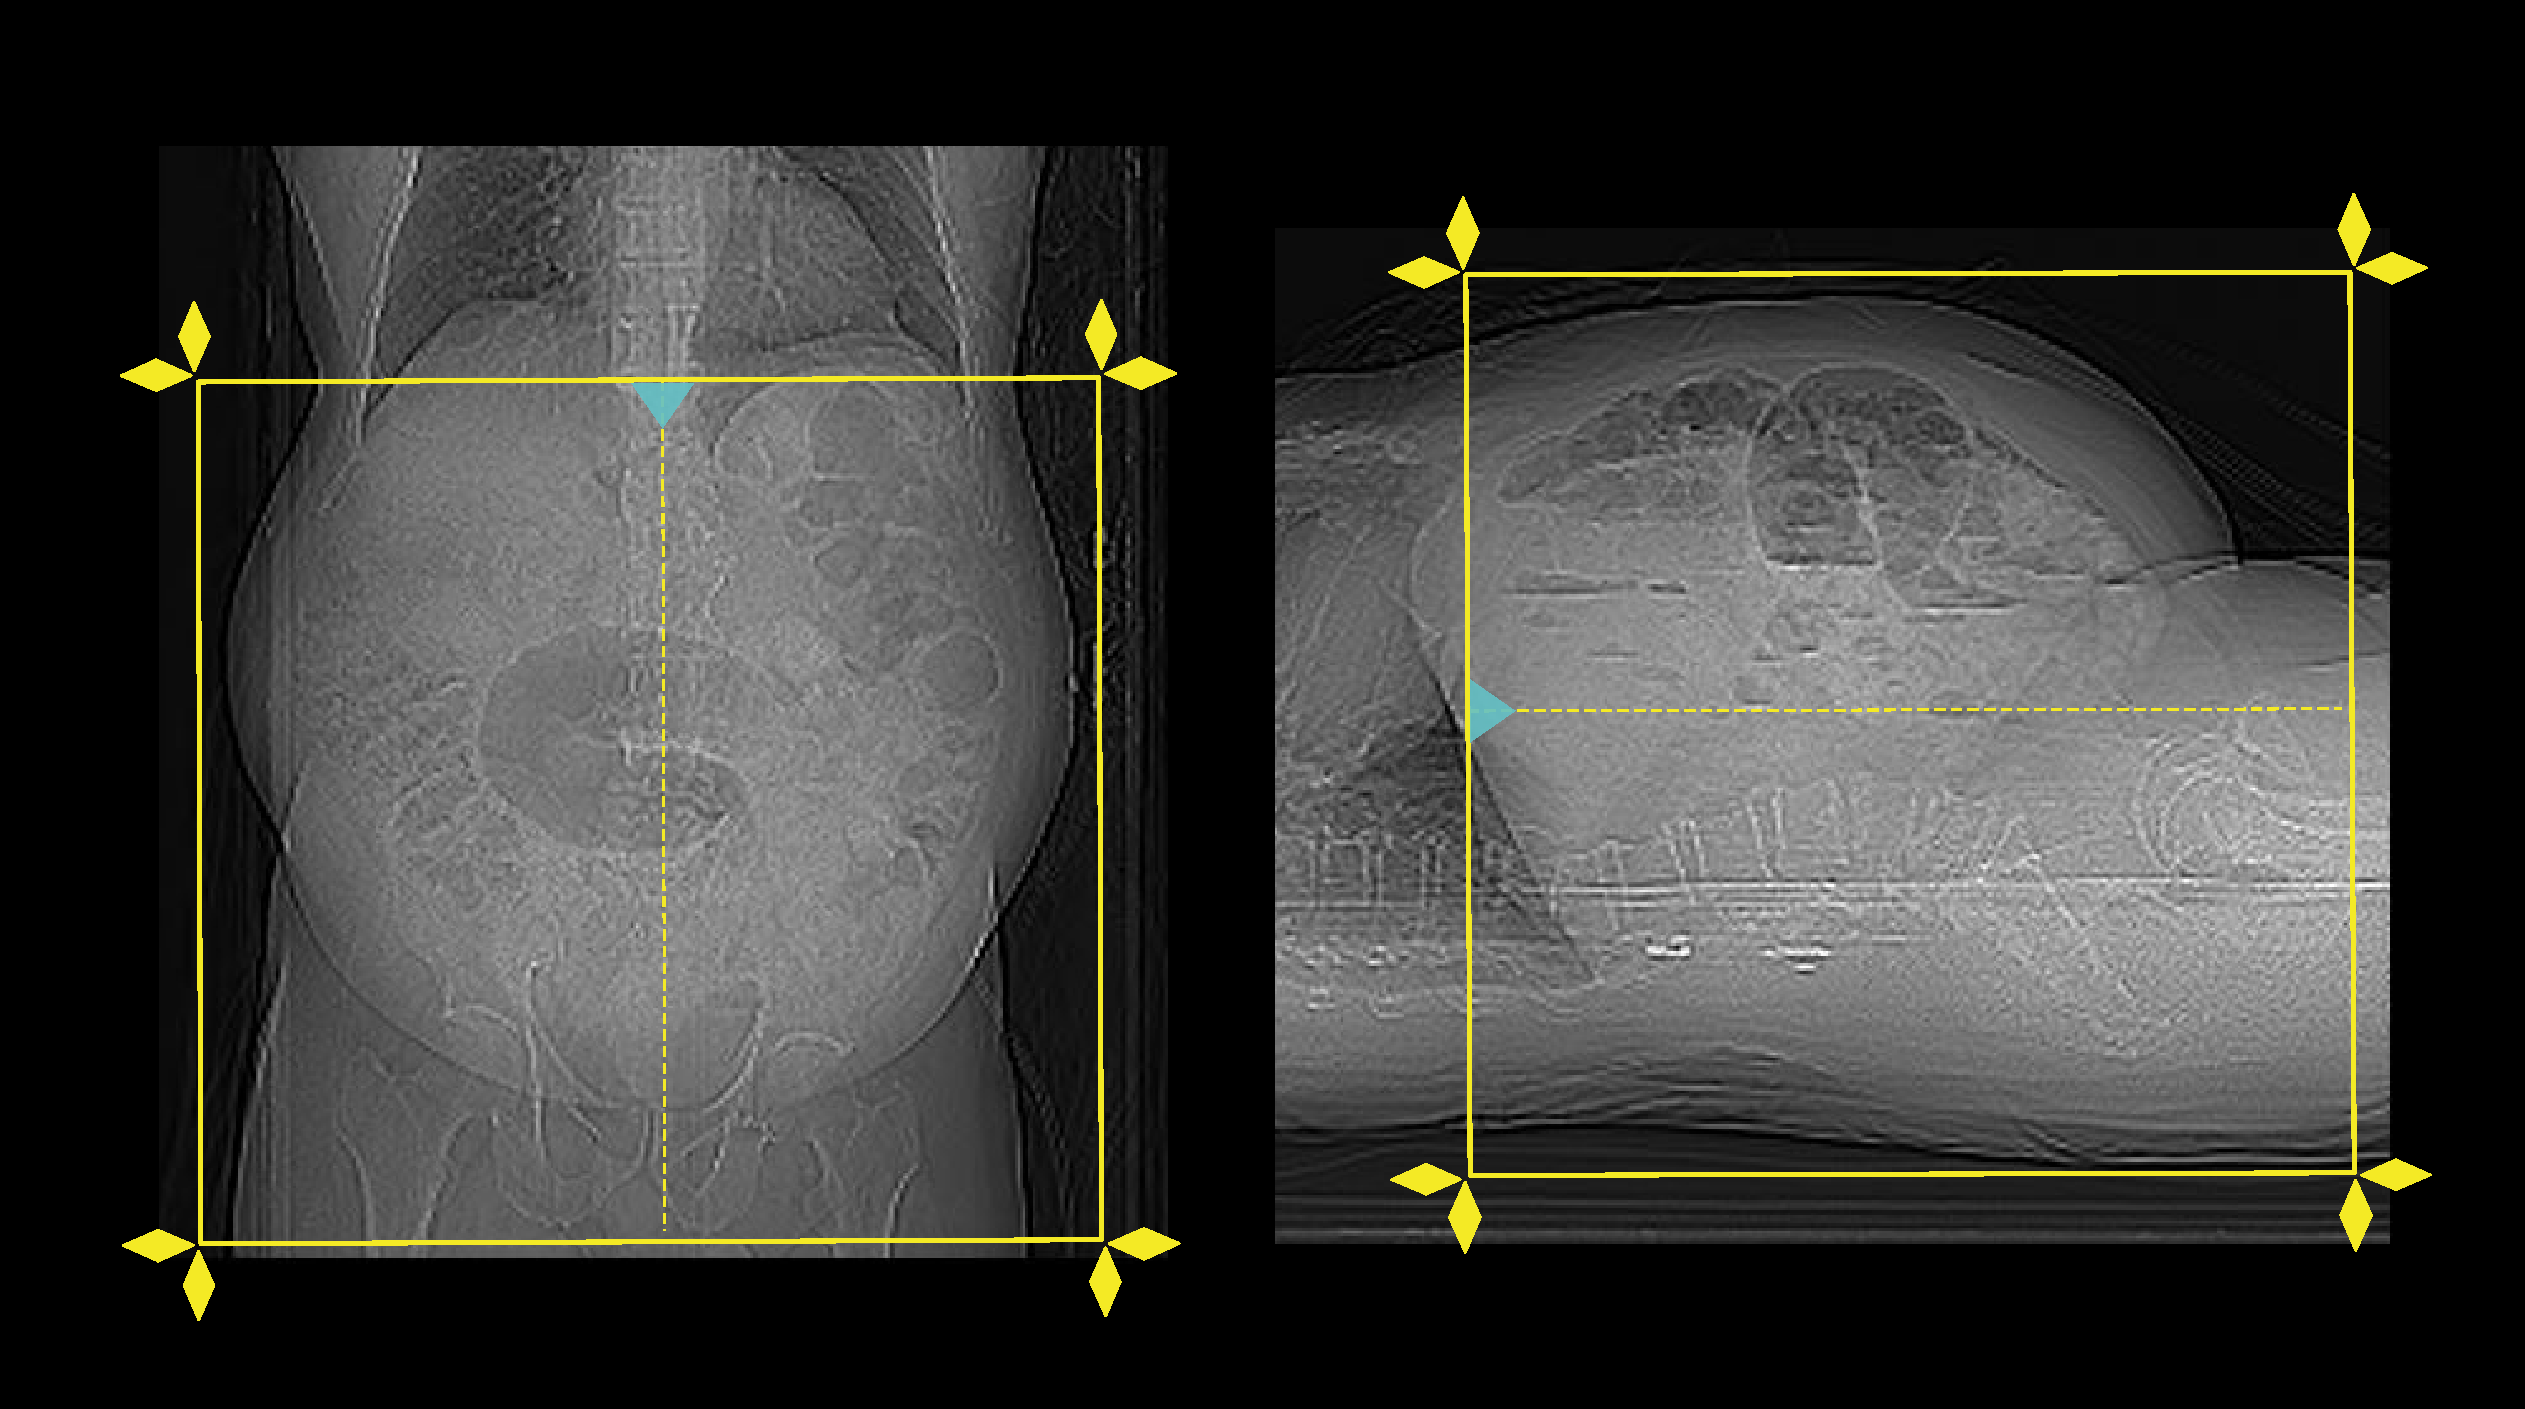

- Set the scout start point at the nipple level and scan direction out of the gantry.

- Plan the scan slab to start above kidneys and to end below pubic symphysis.